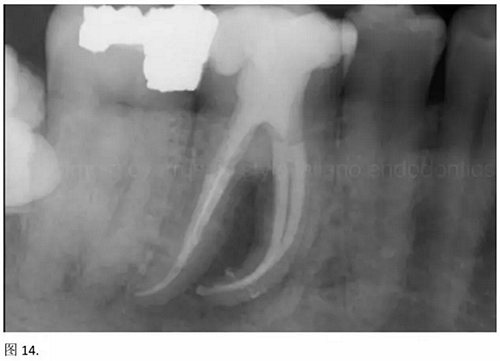

開髓后預(yù)敞、探查根管、建立直線通路是根管機(jī)械預(yù)備的第一步。在這些階段中,醫(yī)生可能會(huì)經(jīng)常遇到一些困難。這些難題包括器械折斷、臺(tái)階形成、根管歧坡或根管拉直、帶狀穿孔、根尖穿孔、根尖肘形、根尖堵塞。所有這些錯(cuò)誤可導(dǎo)致根管系統(tǒng)清潔不完善從而降低牙髓治療成功率。

結(jié)論:本文的目的是描述一種旨在優(yōu)化根管根尖部分預(yù)備的預(yù)敞技術(shù)。根管頸部或冠方的早期預(yù)敞對(duì)于減少初尖銼直徑和根尖部根管直徑之間的差異至關(guān)重要。大量研究表明,手用或機(jī)用器械預(yù)敞根管能顯著減少器械折斷的發(fā)生率。下一篇文章將描述如何建立可重復(fù)的引導(dǎo)路徑。而引導(dǎo)路徑是指鎳鈦器械可沿著光滑根管壁輕易地滑行至工作長(zhǎng)度的通路。